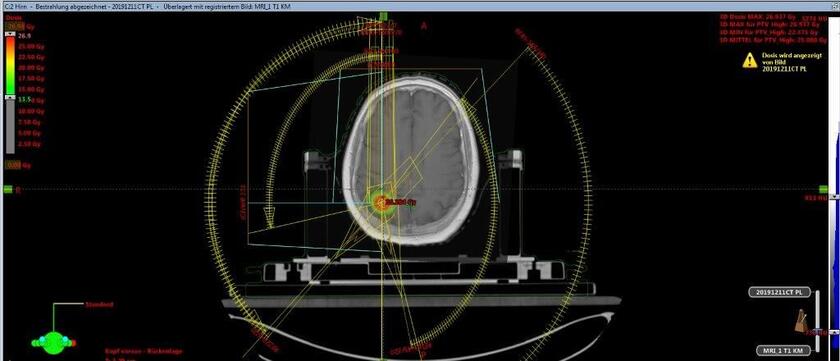

Bestrahlungsplan einer stereotaktischen Präzisionsbestrahlung einer Hirnmetastase.

Stereotaktische Präzisionsbestrahlungen mit hohen Einzeldosen und kurzer Behandlungsdauer führen wir im Schädelbereich (z. B. Hirnmetastasen) aber auch im Körperbereich (z. B. Lungentumore, einzelne Metastasen in Lunge, Leber, Nebennieren, Knochen) und ggf. weiteren Lokalisationen durch.